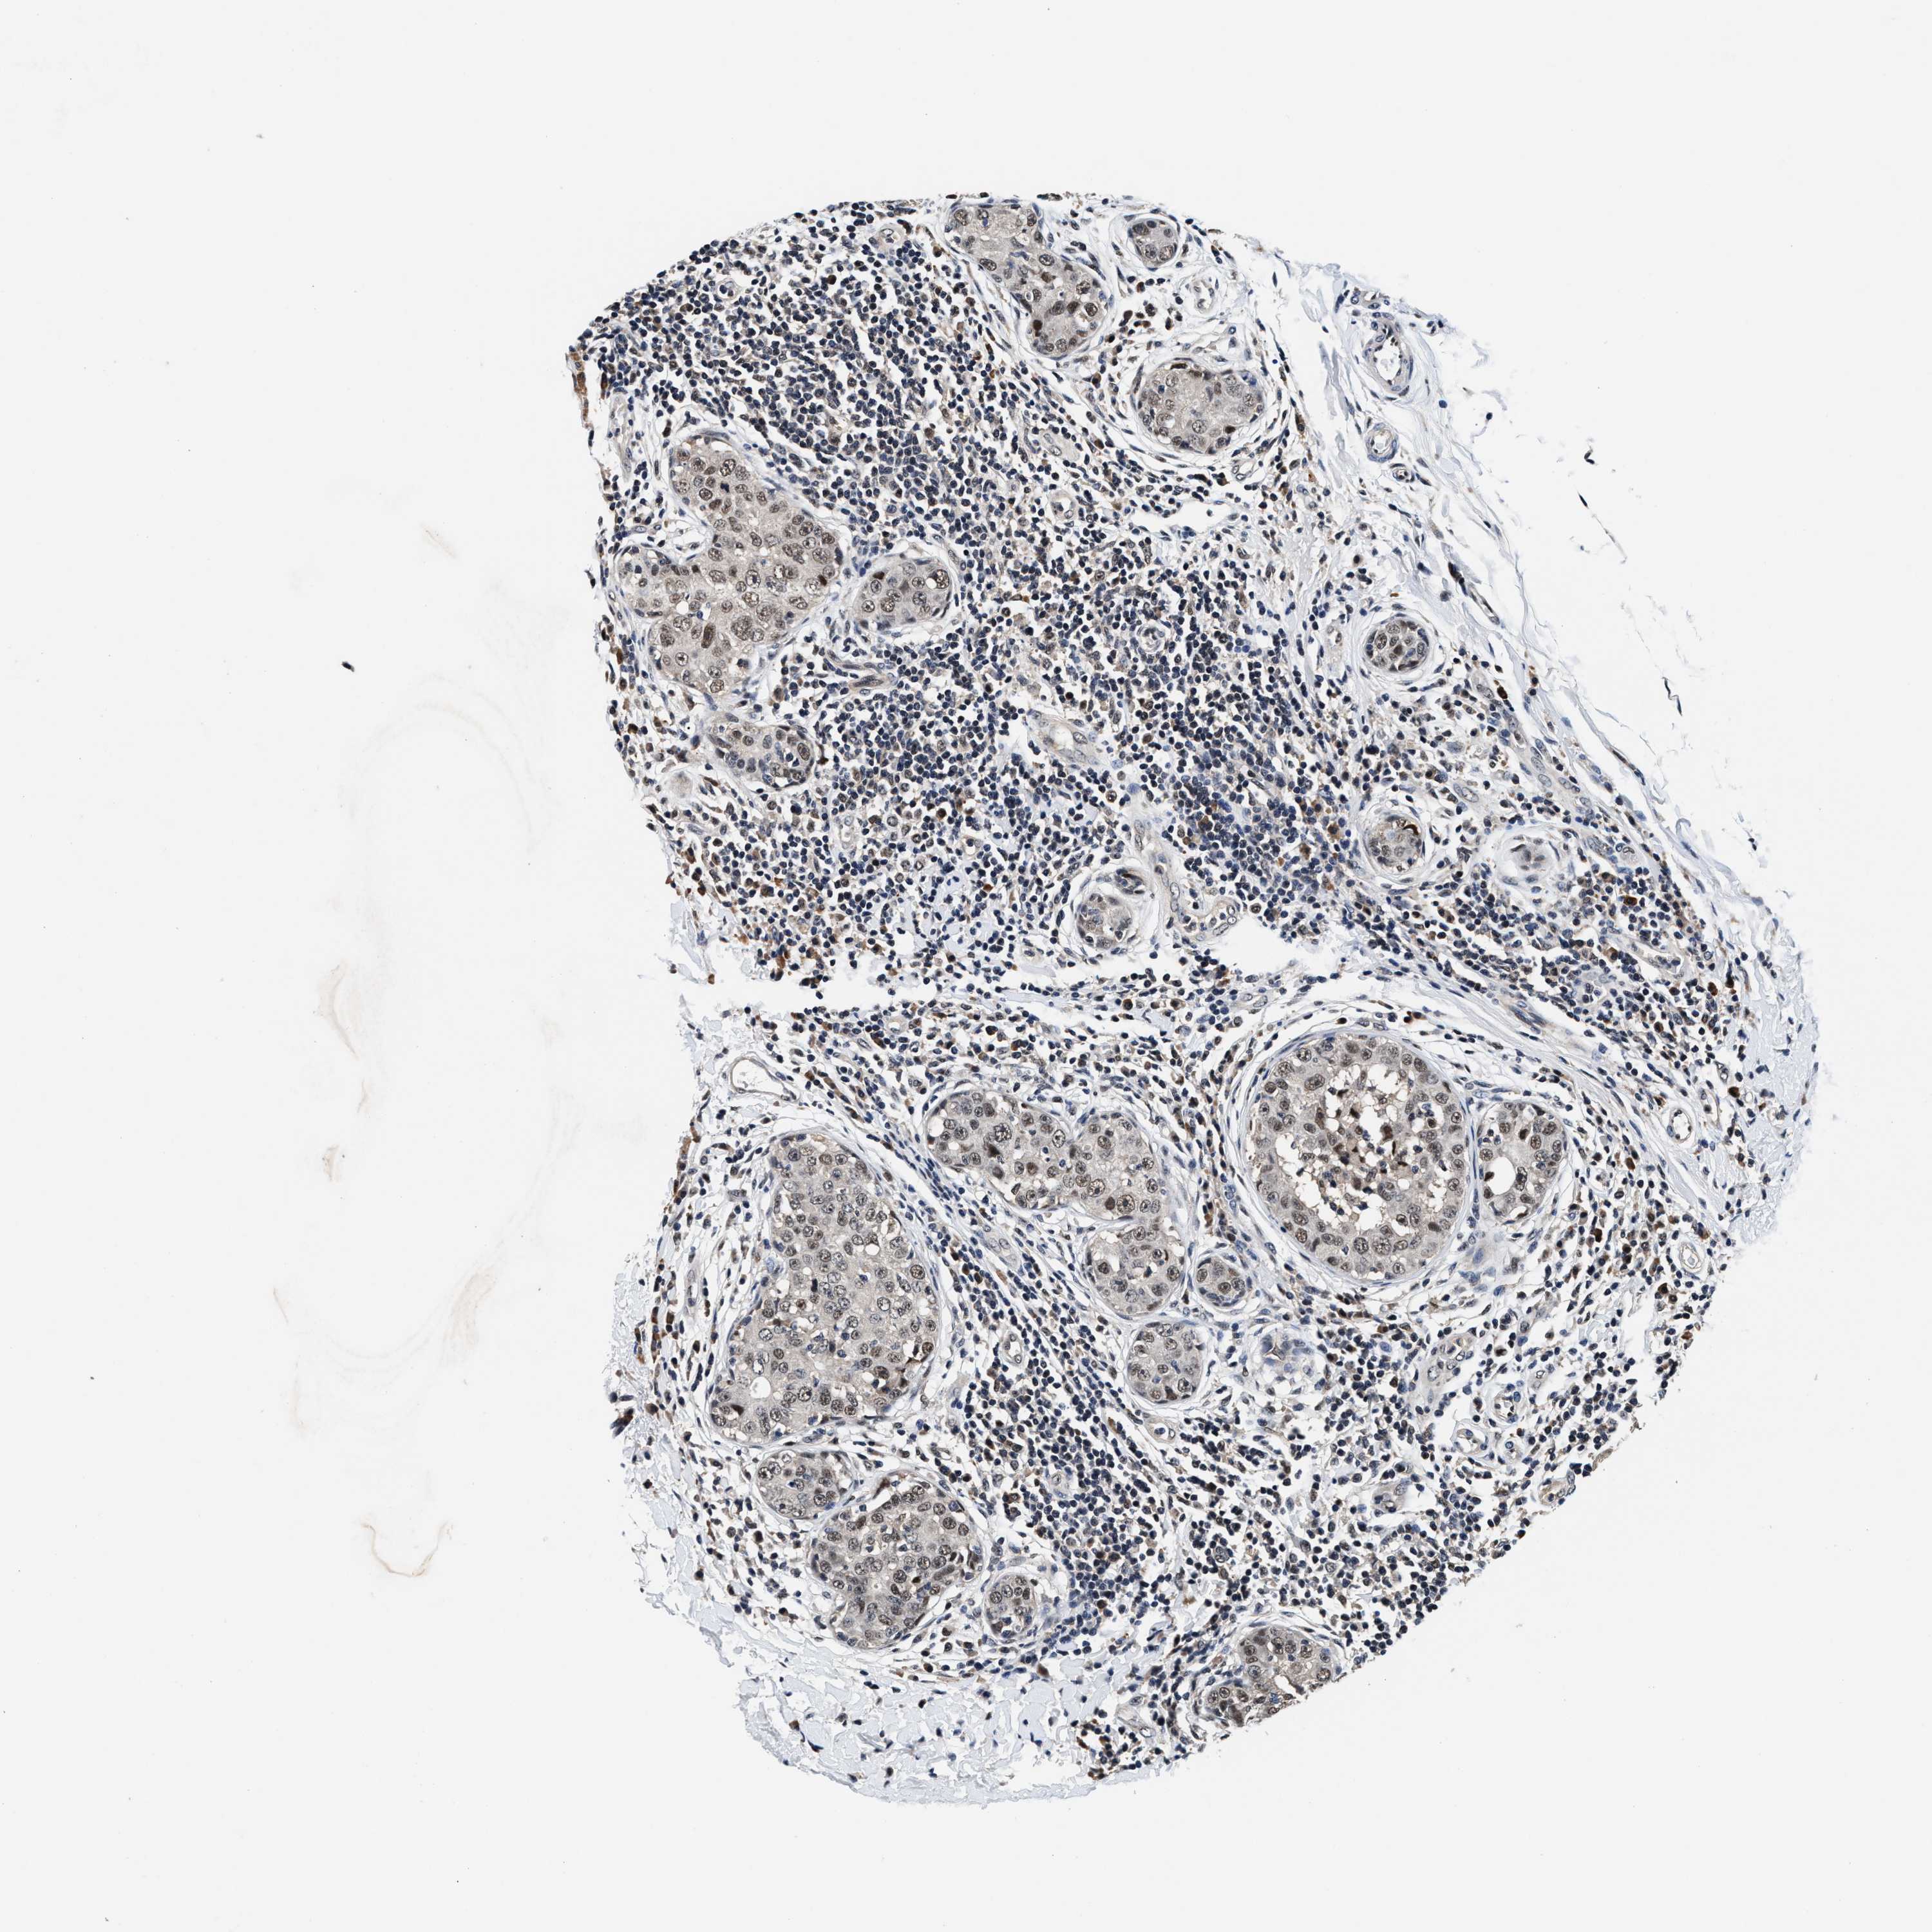

BRCA TCGA BRCA VALIDATION PROTEIN EXPRESSION

ANTIBODIES

AND

VALIDATION